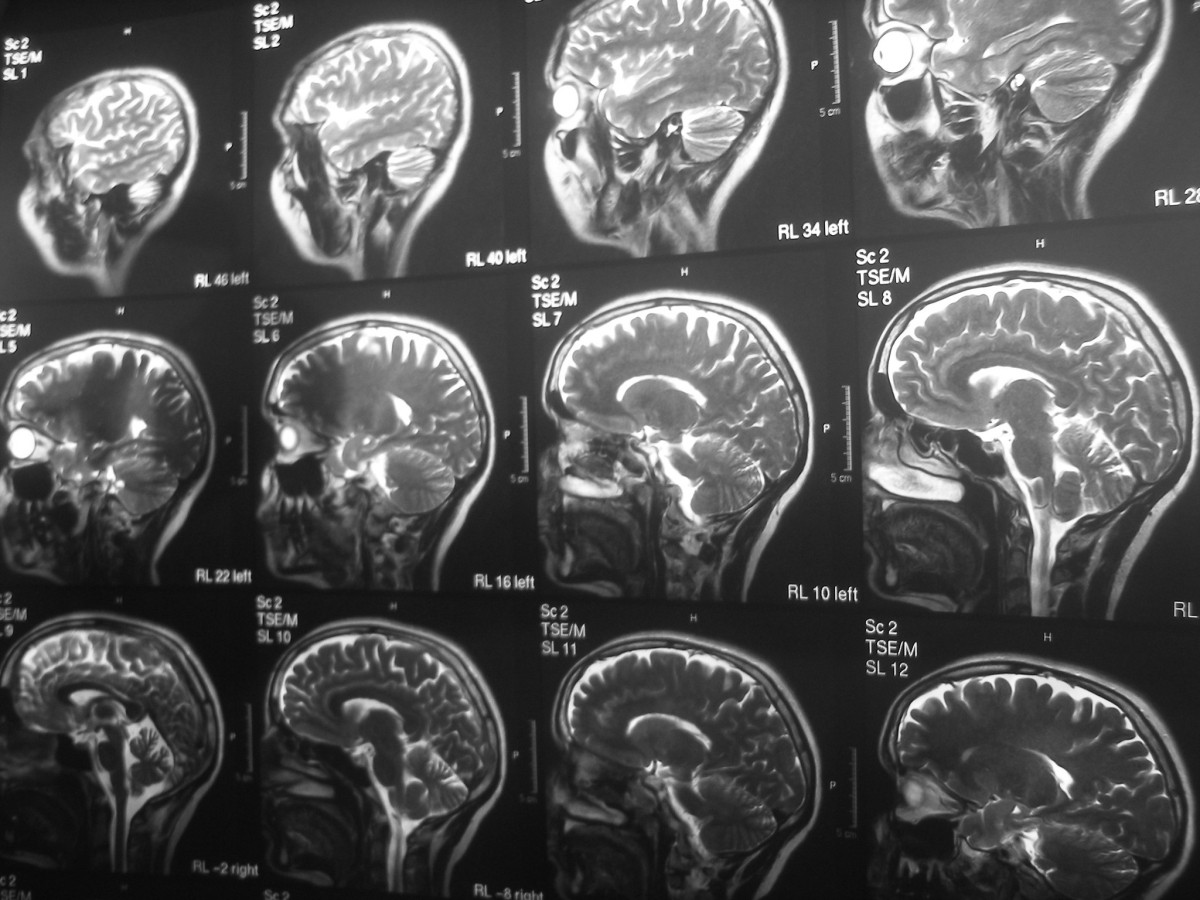

Obecnie kieruję swoją małą grupą badawczą w Zurychu, ale oczywiście wciąż bardzo blisko współpracujemy z Franzem Vollenweiderem i jego grupą. Skupiamy się głównie na obrazowaniu mózgu za pomocą takich technik jak funkcjonalny rezonans magnetyczny (fMRI), elektroencefalografia (EEG), przezczaszkowa stymulacja mózgu (TMS) w połączeniu z elektroencefalografią czy funkcjonalna spektroskopia bliskiej podczerwieni (fNIRS). Zasadniczo używamy więc wielu różnych metod neuroobrazowania, ale oczywiście korzystamy również z oceny behawioralnej i prosimy ludzi o wypełnianie kwestionariuszy dotyczących ich doświadczeń, a następnie próbujemy zintegrować te różne sposoby gromadzenia i analizowania informacji. Dążymy do tego, aby połączyć subiektywne przeżycia z obiektywnymi danymi.

Za pomocą tych substancji możemy w bardzo bezpieczny sposób tymczasowo wprowadzać ludzi w odmienny stan świadomości, co pomaga nam badać świadomość samą w sobie. Kiedy patrzę na obrazy wykonane za pomocą funkcjonalnego rezonansu magnetycznego, pojawia się we mnie głębokie poczucie, że świadomość nie może być ograniczona wyłącznie do jednego ośrodka mózgowego. Jest to niezwykle złożone zjawisko występujące w całym mózgu i nie sądzę, że kiedykolwiek będziemy w stanie wskazać jedno miejsce i powiedzieć: „Tutaj znajduje się świadomość”.